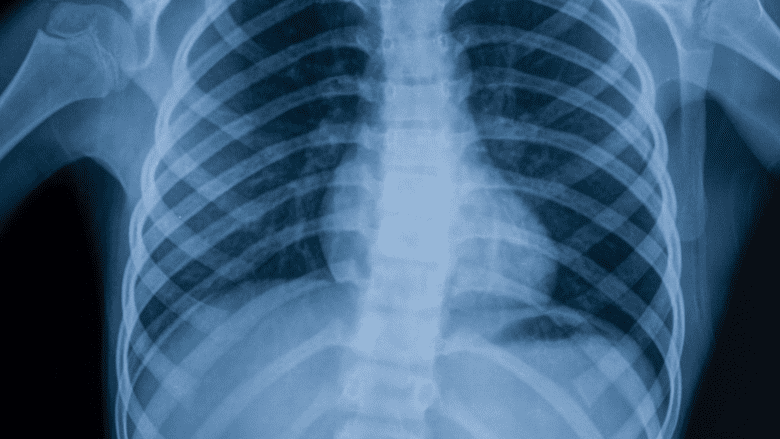

X-ray.  An x-ray shows signs of degenerative changes in the bones, such as bone spurs at a facet joint, a sign that the bones have tried to compensate for cartilage loss with extra bone growth.

There is a high concentration of nerves radiating from the spine, so even minor cartilage damage or bone spurs detected on an x-ray can translate into a lot of pain if it is in a sensitive spot. It is also possible for a person to experience no pain even though their x-rays to show significant signs of spinal osteoarthritis